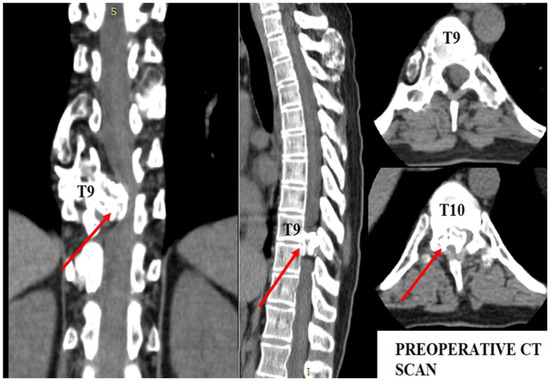

The patient underwent diagnostic evaluations with both MRI and CT scans (Figure 1), with the CT scan being particularly crucial for assessing bone and cartilage tissues, which are primarily affected in this disease. The imaging revealed an intracanalicular lesion at the T9–T10 level, compressing nerve roots and constricting the spinal cord. Additionally, she had osteochondromas at the right humerus, bilateral femurs, right tibia, and hip joints, along with numerous others along the spinal column. She also suffered from bilateral coxarthrosis and gonarthrosis, which severely limited her range of movement.

Figure 1. Preoperative CT scan. Note the intracanalar localization determined by the osteochondroma.

As shown in Figure 1, the osteochondroma occupied roughly three-quarters of the whole caliber of the medullary canal. Using the CT scan, the mass showed a bony signal with a homogenous composition. The shift of the spinal cord was very relevant, as the patient could not walk, or maintain orthostatism or sphincter control.